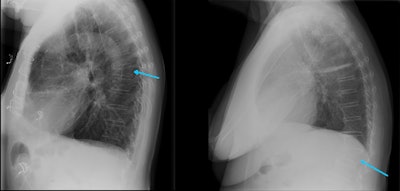

Radiologists and reporting radiographers are well-placed to diagnose VFFs on any modality that can provide images of the spine, including x-ray. All images courtesy of Dr. Anagha Parkar, Bergen, Norway.These are the 12 key points in the RCR guidance:

- Implement a policy of automatic sagittal spinal reformatting and display and storage on PACS for cross-sectional imaging studies that include the spine.

With body CT scanning, performing sagittal bone reformats of the spine does not require additional scan times or radiation dose, nor does it require significant additional storage space. To increase VFF detection on body CT, sagittal reconstruction of the spine using bone windows should be sent routinely to PACS for storage and display."Emerging AI technology and algorithms have scope to support the identification of VFFs through routine scrutiny of cross-sectional imaging via PACS and the creation of 'alert lists' of those patients with suspected VFFs. Radiological interpretation may still be required to verify absence or presence of AI-identified VFFs since this technology is currently limited in differentiating between VFFs and non-fracture deformities such as Scheuermann's disease or Schmorl's nodes," the authors stated.